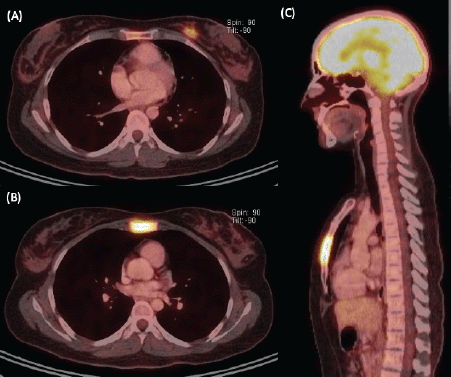

We present the case of a 36-year-old woman, with insulin resistance, without a family history of breast cancer, who consulted for a 6-month evolution self-detected left breast nodule associated with skin retraction. At the physical exam, there was a 20-mm palpable mass retracting the skin at the lower-inner quadrant (LIQ) of the left breast, without clinically evident axillary adenopathies. The patient was studied with mammography [Figure 1] and breast ultrasound [Figure 2], which showed a spiculated mass of 29 × 24 × 14 mm at the LIQ of left breast, with the increased flow at doppler, diagnosed as BIRADS-5. A core biopsy was performed, demonstrating a poorly differentiated invasive ductal carcinoma with positive oestrogen receptor (99%; / ), positive progesterone receptor (90%; ), positive human epidermal growth factor receptor type 2 (HER2) 3 , fluorescence in situ hybridisation for HER2 and Ki-67 30%. The staging study demonstrated an osteolytic lesion compatible with sternal metastasis evident in computed tomography (CT), positron emission tomography (PET)/CT and magnetic resonance imaging (MRI) [Figure 3]. The staging was completed with sentinel lymph node biopsy, obtaining six lymph nodes without metastasis. The primary lesion was marked with two metallic clips guided by ultrasound. The patient completed neoadjuvant ST with Doxorubicin, Cyclophosphamide, Paclitaxel, and HER2-directed therapy with Trastuzumab and Pertuzumab, with a complete clinical response at physical exam and images [Figure 4]. Later, she underwent left partial mastectomy, using percutaneous hookwire for the location of the metallic marker clips. The definitive biopsy demonstrated an area of 27 × 25 × 15 mm of scarring substitutive fibrosis associated with isolated microfocus (less than 1 mm) of moderately differentiated invasive ductal carcinoma with negative margins. The study of residual tumour load reported 1% invasive carcinoma and 0% intraductal carcinoma in situ. Two months after the surgery, LT with radiotherapy was completed. The breast was treated with tangential X-ray fields of 6 and 18 MV, the supraclavicular and left axillary region with a right anterior oblique field, and the internal mammary territory and sternum with an array of photons of 18 MV and electrons of 9 MeV, completing in all areas a dose of 50 Gy in 25 fractions in 5 weeks and then a boost of 10 Gy in 5 fractions over the tumour bed. Subsequently, it was decided to complete ST with Trastuzumab and Pertuzumab, in addition to pharmacological ovarian suppression with Triptorelin plus Tamoxifen. The HER2-directed therapy will be maintained until the progression of the disease or toxicity.

Figure 3. Staging image study. (A) Axial view of PET/CT showing a hypermetabolic left breast nodule of 18 mm at the LIQ, compatible with primary neoplasia. (B) Axial and (C) sagittal views of PET/CT demonstrating extensive substitutive hypermetabolic sternal compromise with cortical osteolysis (maximum SUV 7.7).